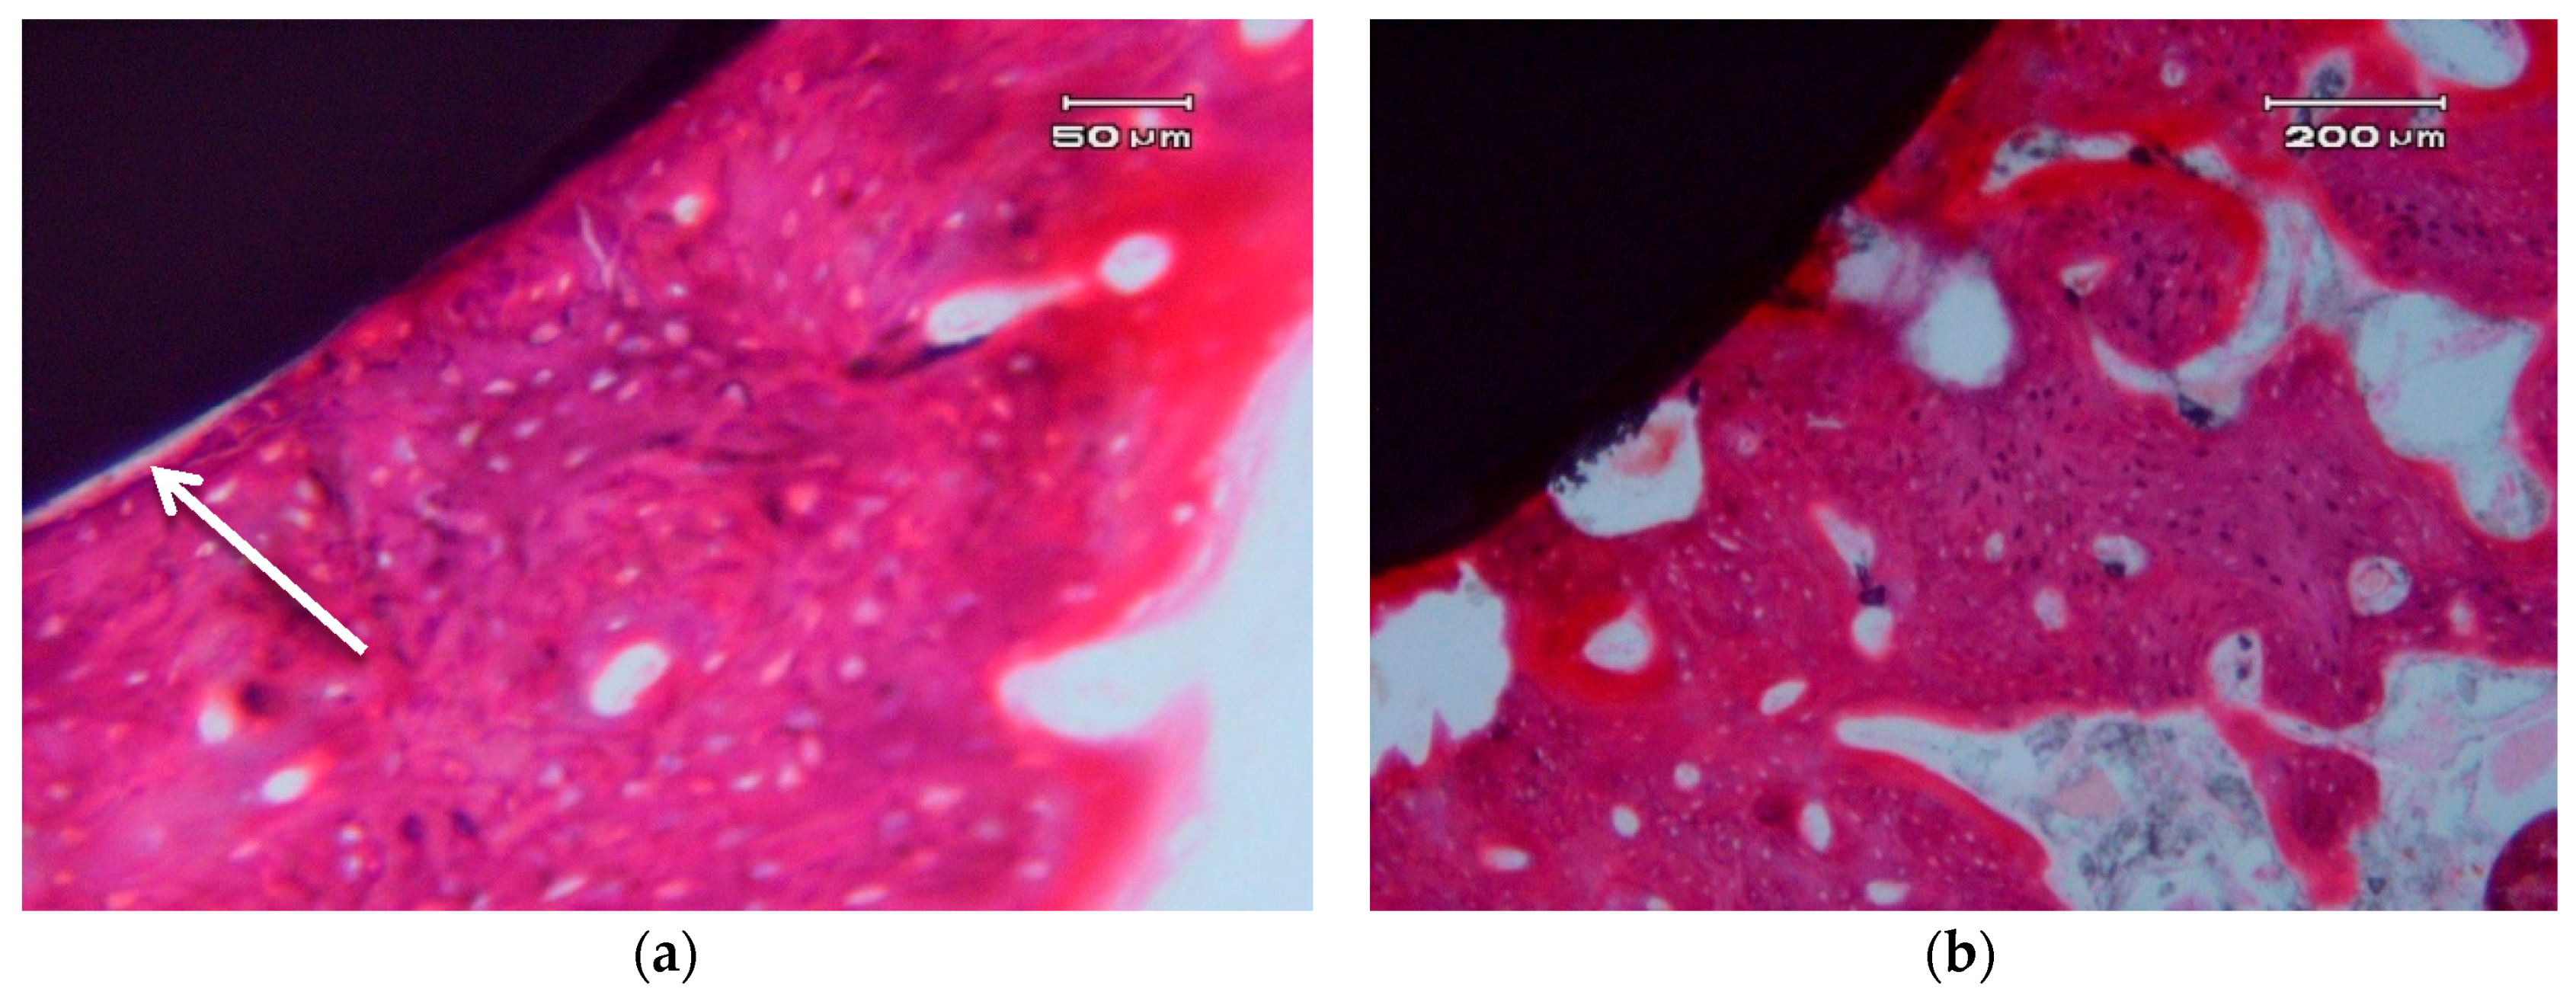

Figure 5 shows the photographs correspond to a transversal cross-section of implant.

Transversal cross-sections of different nanocomposite ZCe-A implant-bone interfaces after eight weeks of healing. (a,b) show two different interfaces.

In general, we can clearly appreciate bone growth in direct contact with the surface of the implant. There are some areas that present a small gap of less than 5 µm, which can be due to an artefact of the histological process (see arrow in Figure 5a). There is no connective tissue interposed between the surface of the implant and the bone. There are no signs of inflammation at the interface or of adjacent bone. The bone that is in contact with the implant shows, in some areas, very few characteristics of immature bone and a typical woven bone cell distribution (plexiform) (Figure 5b), although it mostly consists of laminar and haversian bone. There are no images of bone sequestration, nor atypia or dysplasia.